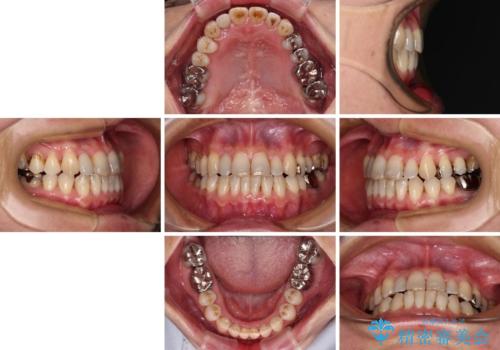

- 前歯の反対咬合を気にして来院された患者様です。

上顎骨の幅が下顎骨よりも小さいので、拡大装置により骨幅を広げて上下関係を改善すると同時にワイヤー矯正で反対咬合の改善を図り、その後インビザラインにて歯並びを整えることとしました。

急速拡大装置の使用により奥歯の咬み合わせが劇的に変わり、その変化を利用して反対咬合を改善することができました。

治療期間中は奥歯が咬み合わず、食事が取りにくいなどの不都合がありましたが、最終的にはきれいに整えることができました。